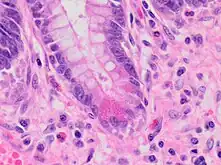

| A micrograph demonstrating cryptitis, a microscopic correlate of colitis. H&E stain. | |

An important investigation in the assessment of colitis is biopsy for histopathology. A very small piece of tissue (usually about 2mm) is removed from the bowel mucosa during endoscopy and examined under the microscope by a histopathologist. A biopsy report generally does not state the diagnosis, but should state any presence of chronic colitis, give an indication of disease activity, as well as state the presence of any epithelial damage (erosions and ulcerations).[4]

Histopathology findings generally associated with chronic colitis include:[4]

Crypt degeneration

Crypt branching and other architectural distortions

Paneth cell (pictured) or gastric metaplasia (only applies in the left colon and rectum)

Other findings include basal plasmacytosis and mucin depletion.[4] Histopathology findings generally associated with active colitis include:[4]

Neutrophilic cryptitis (neutrophils within crypt epithelium)

Crypt abscesses (luminal neutrophilic aggregates)

Gland destruction

Ulceration (seen here as absence of epithelium, and granulation tissue with many fibroblasts)